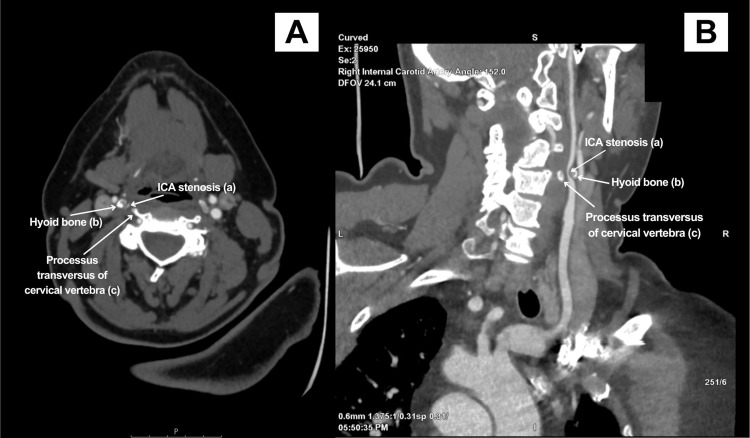

Case report: In this article, we describe the clinical case of a 48-year-old woman who presented with sudden-onset weakness in her left arm. Imaging studies demonstrated acute ischemia in the territory supplied by the right middle cerebral artery. Further evaluation with computed tomography angiography revealed compression of the right internal carotid artery by the hyoid bone. However, additional imaging studies, including digital subtraction angiography and carotid Doppler ultrasound, did not reveal any signs of internal carotid artery stenosis. This suggested that the compression was functional, occurring only in specific positions of the head or arms. The patient was also newly diagnosed with Moyamoya syndrome, characterized by progressive stenosis of the intracranial vessels. Prompt recognition of these findings enabled timely management, including the initiation of antiplatelet therapy.